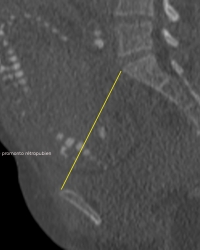

Pelviscanner

La pelvimétrie par scanographie est largement reconnue et utilisée depuis plusieurs années. La précision des mesures et la rapidité d'acquisition des coupes ont contribué à substituer de plus en plus cette technique à la pelvimétrie classique.L'apport du scanner hélicoïdal, encore rehaussé par les appareils multibarrettes, ouvre la possibilité d'examiner la morphologie du bassin et de réaliser très rapidement une pelvimétrie fiable et économe en irradiation.